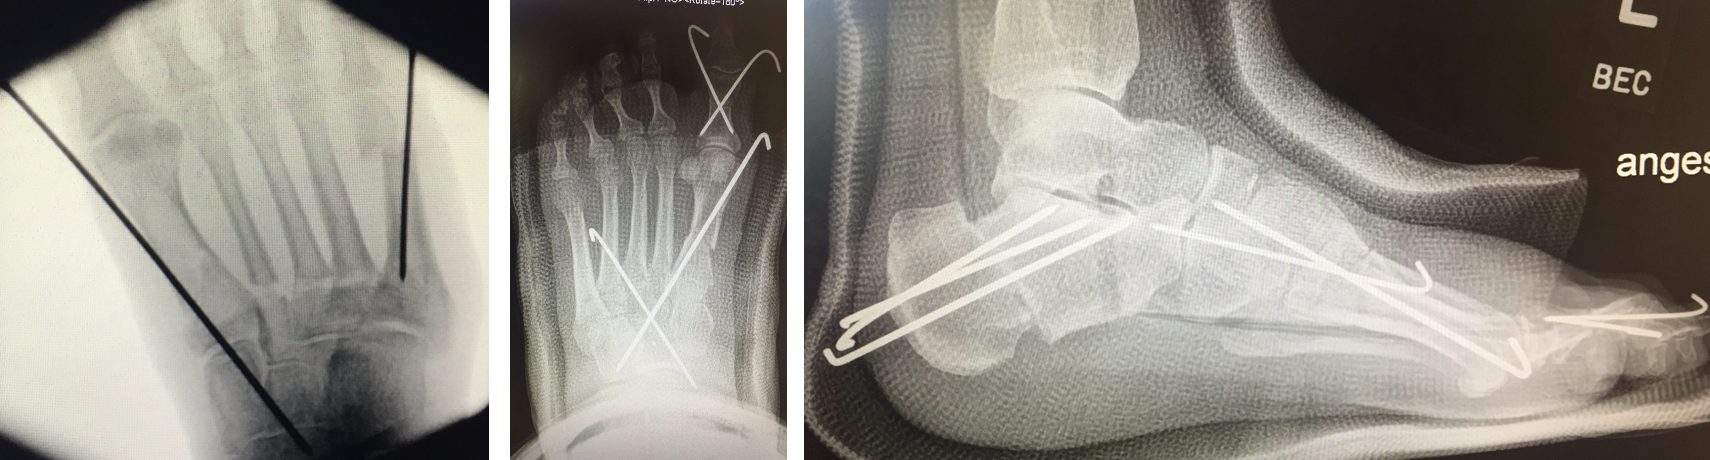

Chevron Osteotomie

Die Chevron Osteotomie 1 ist ohne Komplikationen am wachsenden Skelett durchführbar. Das Metatarsale I besitzt distal keine Wachstumsfuge, die geschädigt werden könnte. Die „französische Methode nach Marc Elkaim“ eignet sich für Kinder ganz besonders (Abb. 28).

Abb. 28 a-g: Radiologischer Verlauf einer Chevronosteotomie nach dem Verfahren von M. Elkaim mit prä- (a-c drei unterschiedliche Ansichten) und intraoperativen Röntgenbildern in zwei Ansichten (d-e) sowie postoperativ zwei Ansichten (f-g).

Zum Lesen der Bildbeschreibung und zur Vollansicht bitte die Bilder anklicken. Bilder: A. Helmers.

Sie wird über eine eigene Tapetechnik fixiert und kann bei einem erhöhten Intermetatarsale-Winkel alternativ zur Scarf-Osteotomie durchgeführt werden. Nachteile der Methode sind eine deutliche Verkürzung durch die Fräse sowie eine starke Plantarisierung des Metatarsale I Köpfchens. Um die Verkürzung zu vermeiden, wird verlängernd in Richtung des Metatarsale II Köpfchens (nicht wie offen in Richtung Metatarsale IV Köpfchen) osteotomiert. Gleiches gilt für die starke Plantarisierung, die durch den Knochenverlust der Fräse entsteht. Die Korrektur eines kindlichen oder jugendlichen Hallux valgus ist mit der Methode ansonsten suffizient durchführbar. Wird verkürzt, muss ausreichend plantarisiert werden, um eine Transfer-Destabilisierung MT II-IV zu vermeiden.

Die MICA-Technik sollte bei geschlossenen Fugen mit einem weitem intermetatarsale Winkel durchgeführt werden. Die dafür typische Verschraubung der Osteotomie kann bei geschlossenen Fugen ohne Probleme erfolgen. Diese Osteotomie kann gut mit einer Akin- und den beschriebenen Kleinzehen-Osteotomien kombiniert werden.